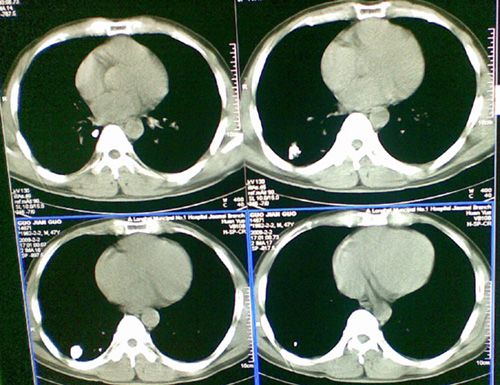

像肺结核钙化吗,不曾见过的影像,请大家帮忙看一下

陈旧性肺结核,钙化。

右肺结核(以纤维增殖、钙化病灶为主)。